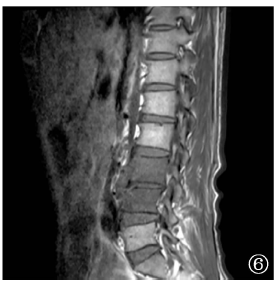

| 图6 病例4,男性,62岁。2018年8月22日于外院摄腰椎MRI,显示腰3~4椎体前缘变尖、椎间隙狭窄,可见斑片状短T1、长T2信号影,压脂序列呈高信号,增强扫描明显强化,T2加权成像显示部分椎间盘信号降低,腰3~4椎间盘组织向椎体后方突出,硬膜囊轻度受压,椎管无狭窄 |